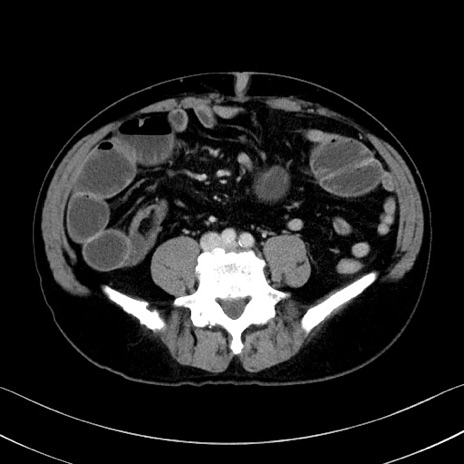

症例35(横断像)

【症例】70歳代 男性

【主訴】腹部膨満、嘔吐

【現病歴】昨日より腹部膨満感出現。本日増悪し、仙痛出現。嘔吐あり、受診。

【既往歴】糖尿病、胆摘後

【身体所見】BP 149/80mmHg、HR 74/min、BT 35.9℃、腹部:膨満、軟、圧痛なし。腸雑音減弱あり。上腹部正中切開瘢痕あり。

【データ】WBC 13500、CRP 1.72